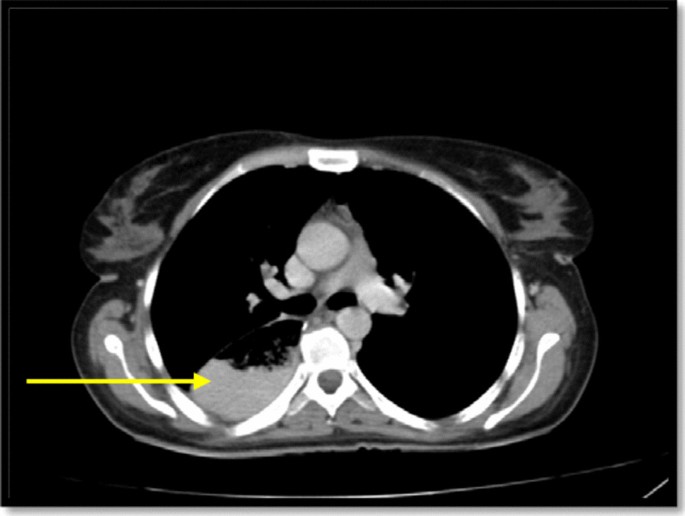

In spiral chest CT scan with and without intravenous (IV) contrast, obtained axial images, represented a 29 × 18 mm soft tissue fullness at middle to distal esophagus (at the level of the carina to the level of the main pulmonary artery), which was suggestive for a tumoral lesion. No lung metastasis was found. In spiral abdomen and pelvic CT scan with oral and IV contrast, there was a 12 × 9 mm LN within gastrohepatic ligament (Fig. 2). In the abdomen and pelvic sonography, there was a 10 × 9 mm hypoechoic lesion between the left liver lobe and greater curvature which was suggestive of lymphadenopathy (LAP) (Fig. 3.).